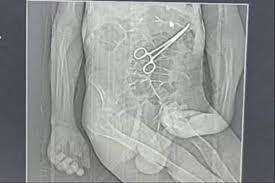

Tomografia usada pela família para acusar médicos de hospital de João Pinheiro (MG) de deixar pinça no abdômen do idoso após cirurgia

Após a cirurgia, o paciente voltou a apresentar sintomas graves, o que levou à realização de novos exames. Nesse momento, uma tomografia identificou, segundo a secretaria, "um corpo estranho na cavidade abdominal".

Os parentes também afirmam que só souberam do que de fato havia ocorrido por meio de uma reportagem de uma rádio local, quando tomaram conhecimento da imagem de uma tomografia indicando uma pinça no abdômen de Manoel.